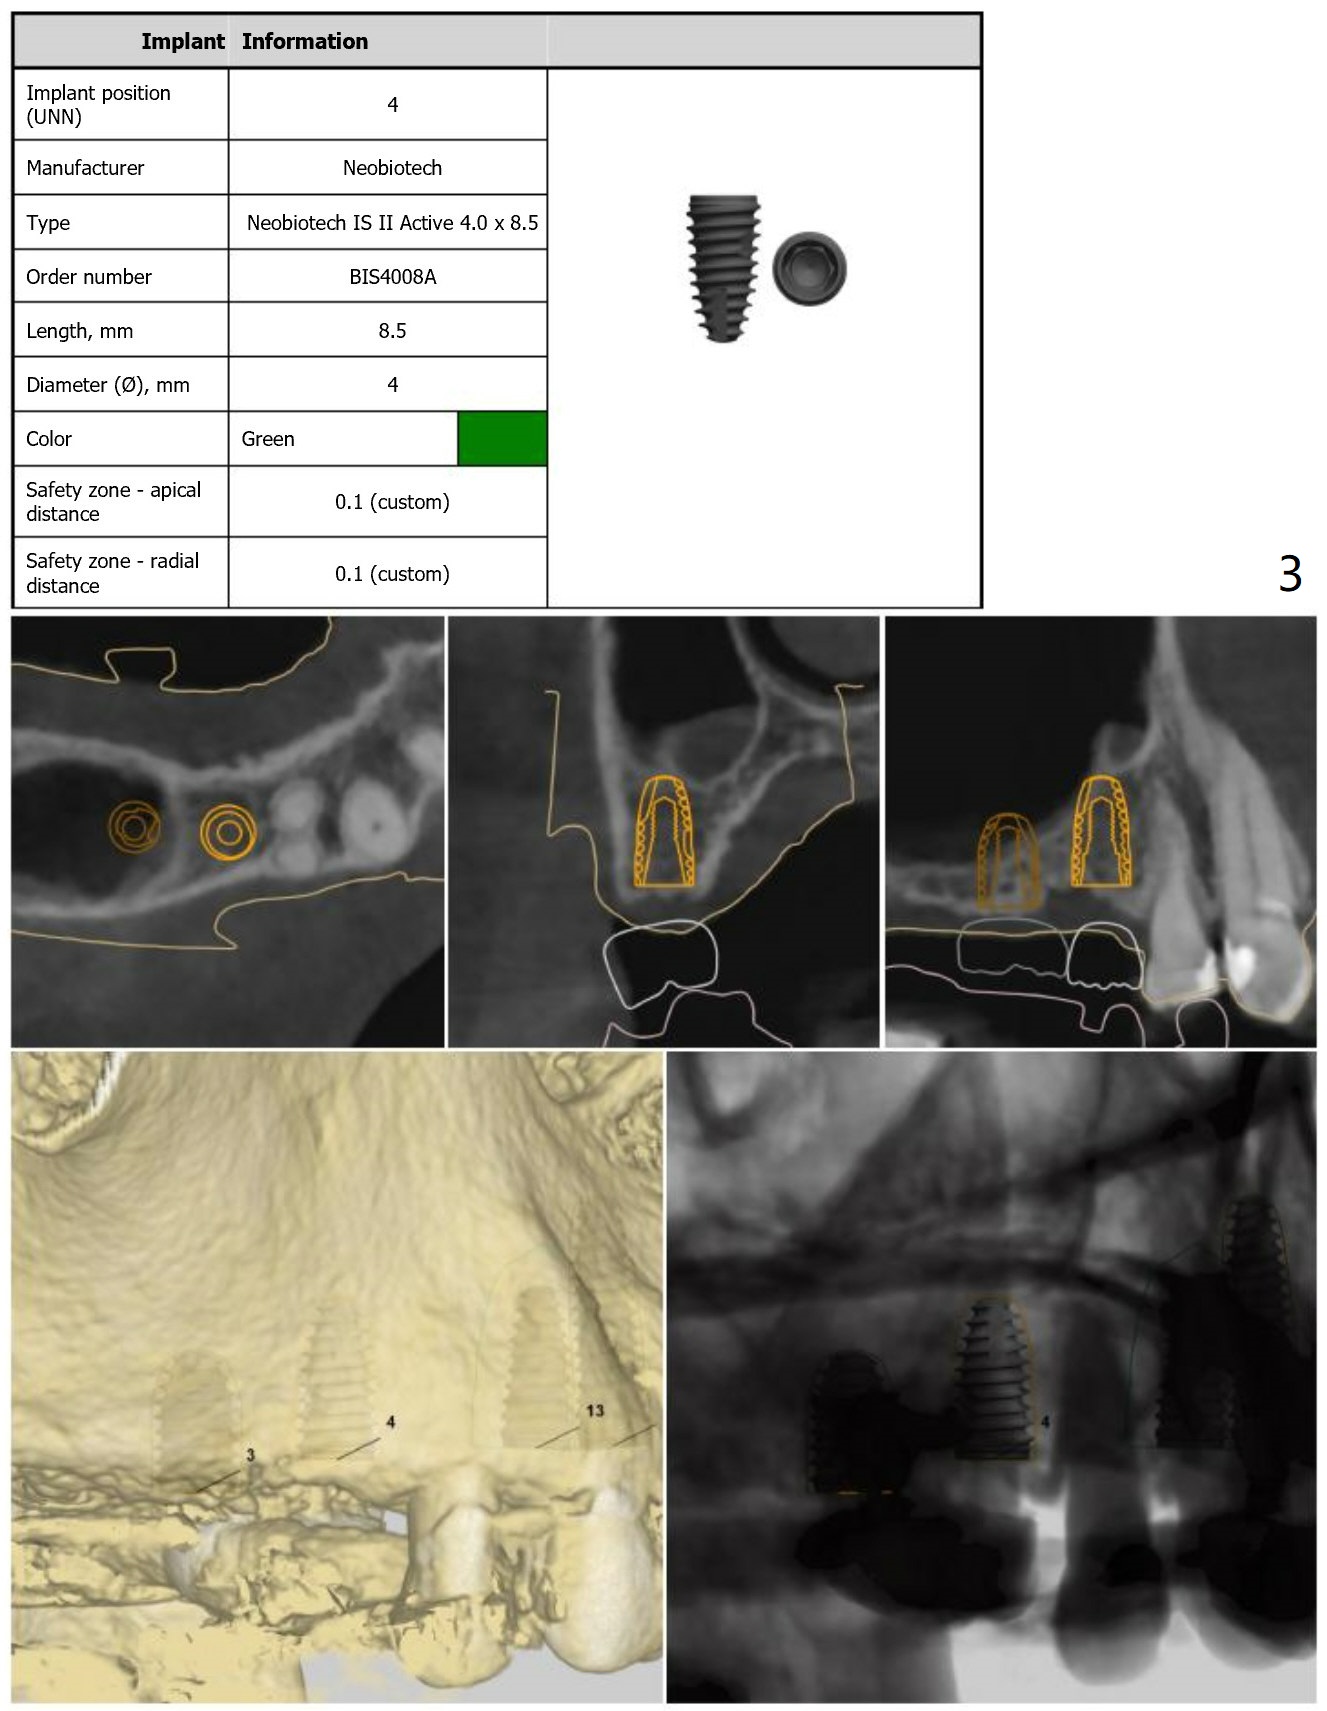

Guide for Sinus Lift

Return to Upper Arch Immediate Implant, Trajectory, No Antibiotic